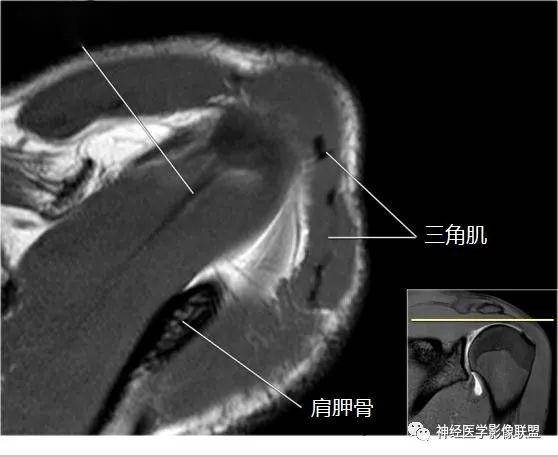

肩关节斜冠状面mr断层解剖

图片尺寸750x527

mri表现:sis的mri表现主要分为两个部分,一是发现肩峰下撞击的原因,二

图片尺寸640x448